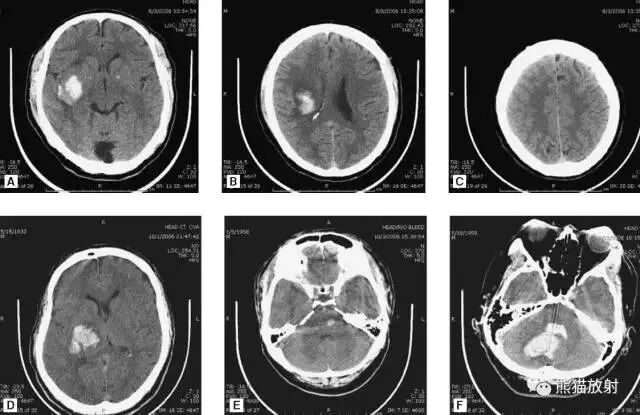

动脉瘤破裂导致蛛网膜下腔出血、

脑室积血、非交通性脑积水。

与外伤性蛛网膜下腔出血不同,动脉瘤破裂导致的SAH常不累及大脑凸面,而位于基底池附近。脑动脉瘤常位于鞍上池的Willis环血管。

A:四脑室积血;

B:中脑导水管、环池、右侧侧脑室颞角积血,前交通动脉处(动脉瘤好发位置)出血密度较高;

C:三脑室积血;

D-F:侧脑室积血,蛛网膜下腔出血(血液代替了脑脊液)。

高血压性脑出血:

- 自发性出血;

- 继发于长期高血压及慢性血管病;

- 常见于基底节区、丘脑、脑桥、小脑。

A:占位效应,相邻脑沟、脑池消失;

F:脑出血破入四脑室。